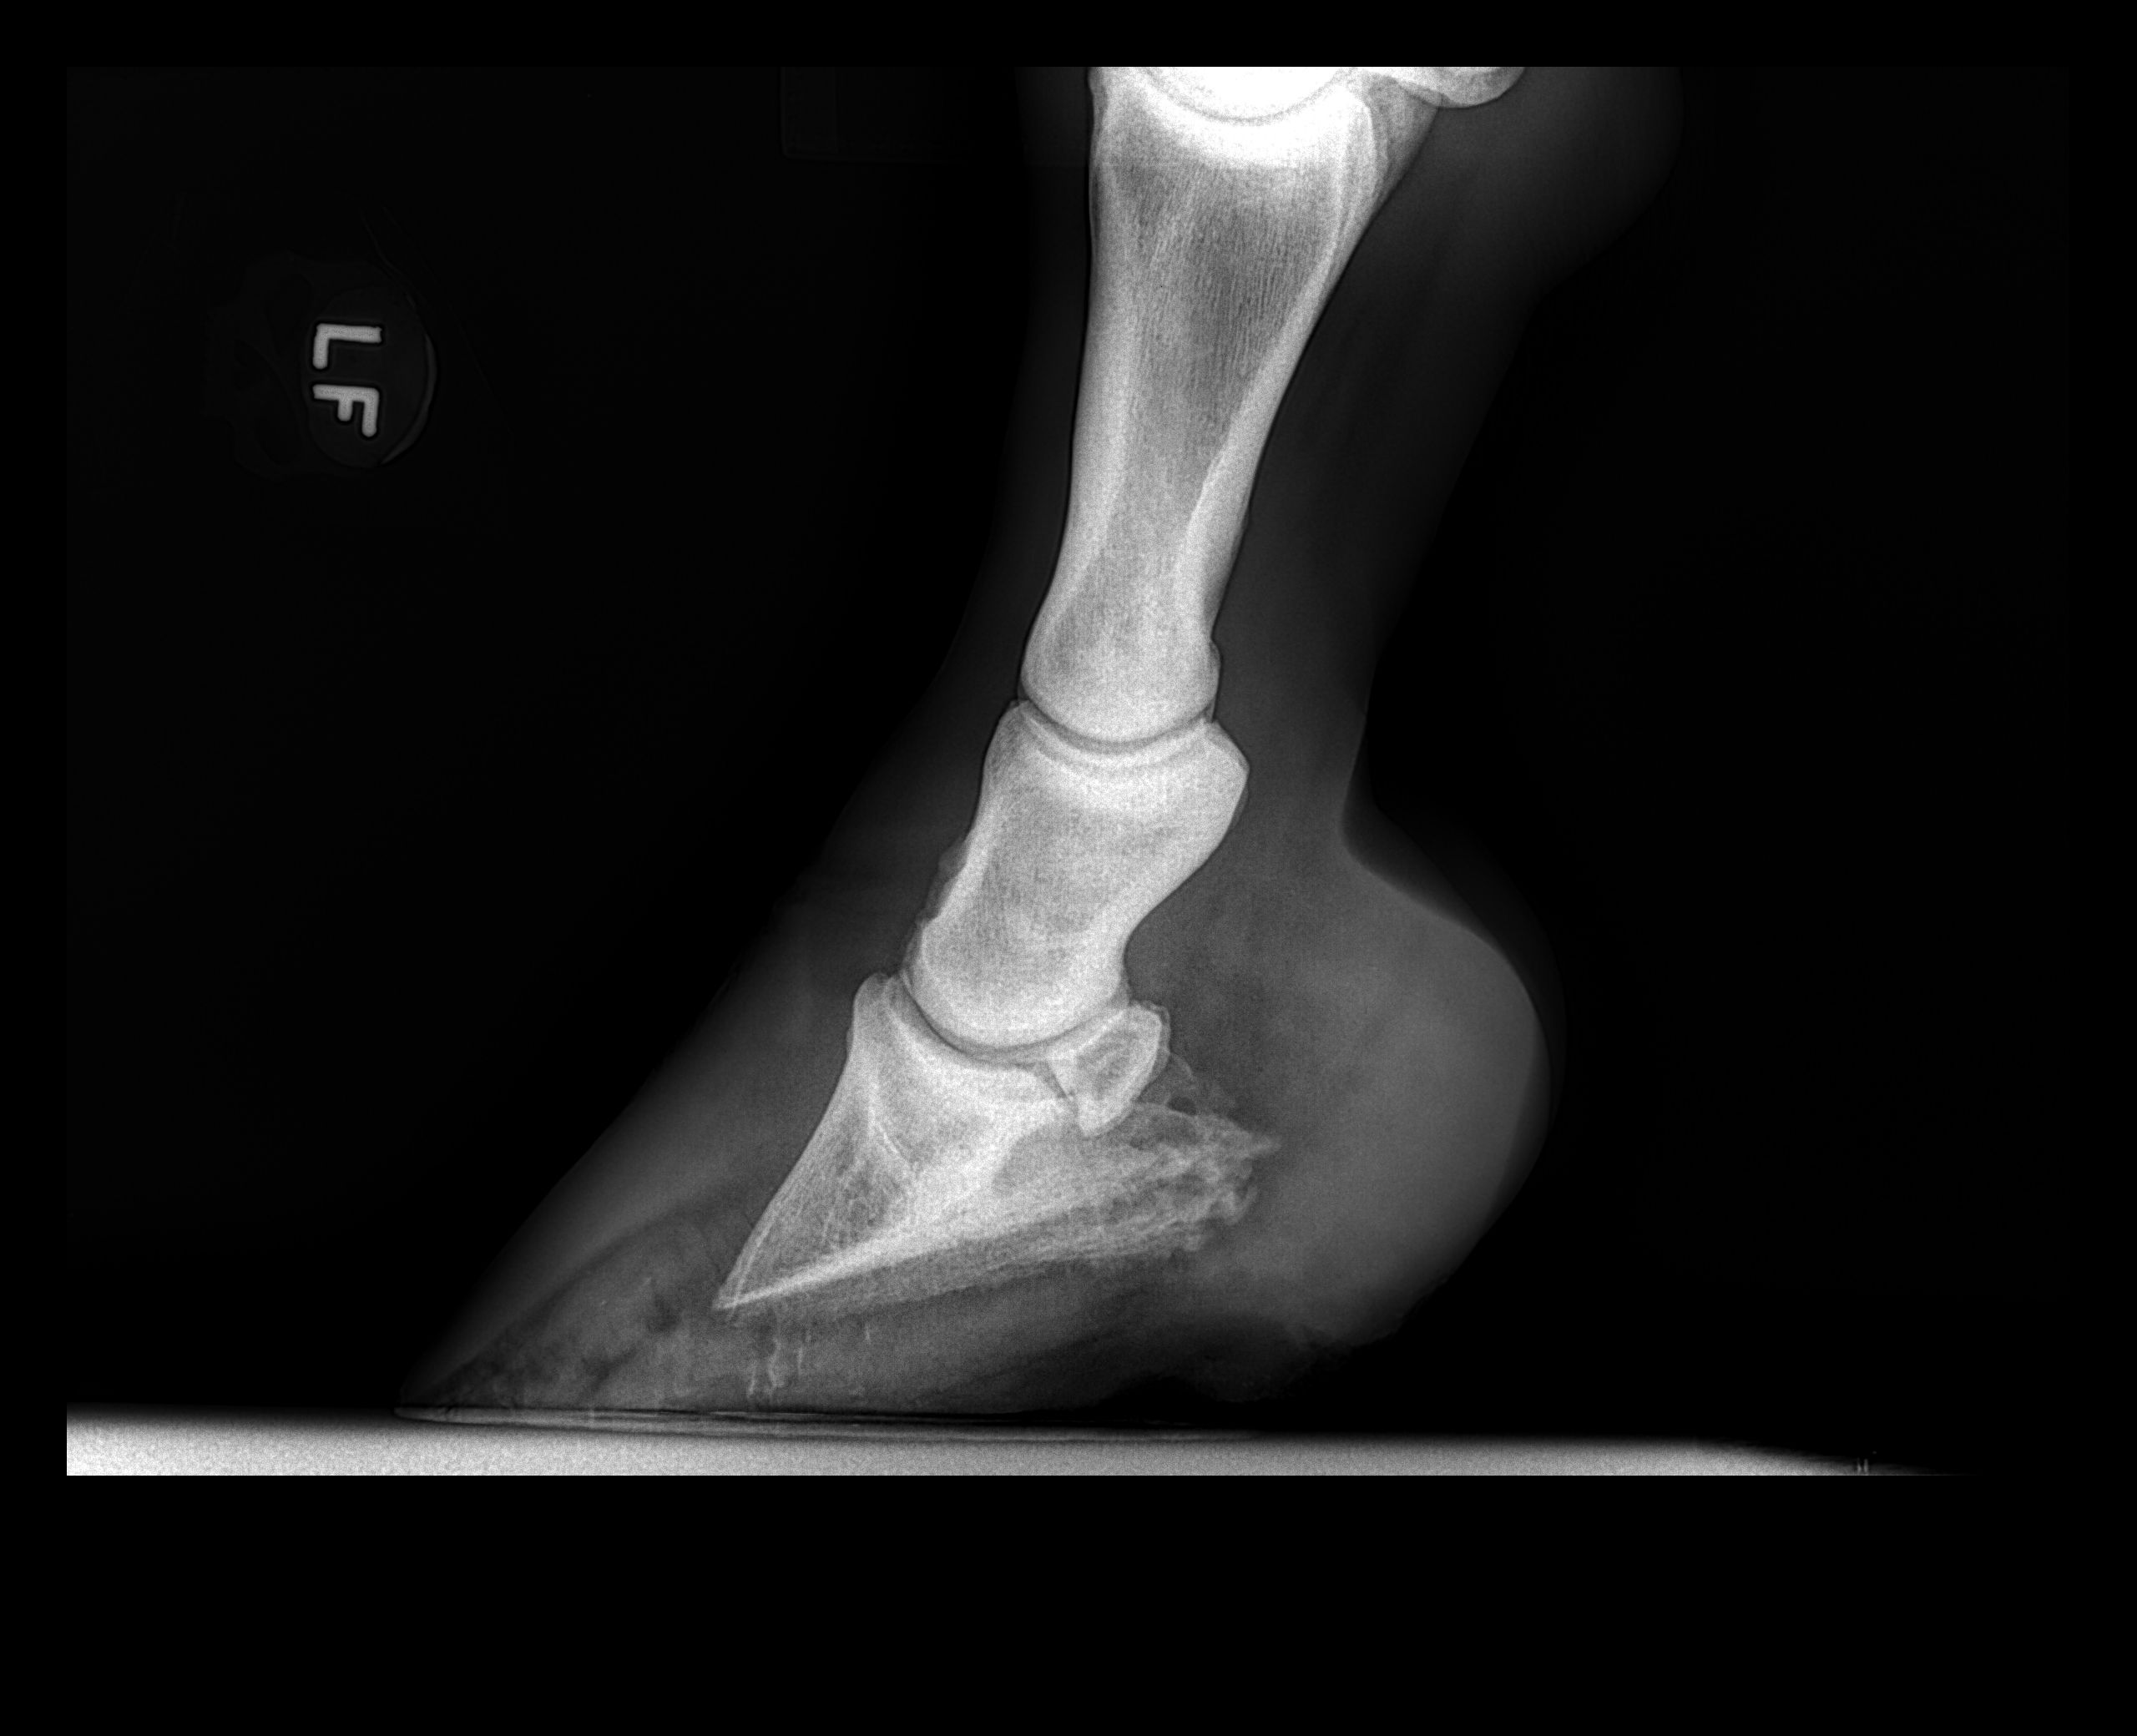

X-ray of laminitic hoof with significant coffin bone rotation

Laminitis in horses

A painful foot condition, laminitis can be the result of various disease processes. Once a horse has had a bout of laminitis, they may be more susceptible to future episodes, which is why recognition and prompt treatment of laminitis is critical to achieving the best possible outcome.